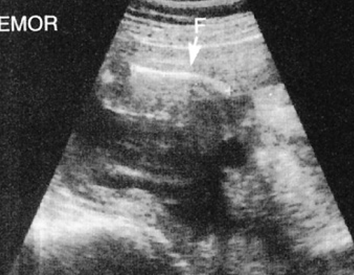

hydronephrosis